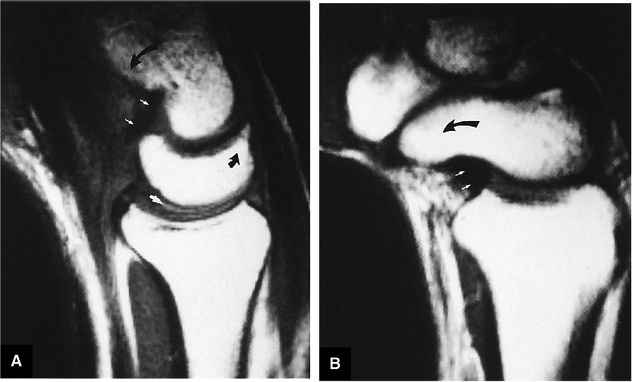

FIGURE 10.89 ● (A) DISI with dorsal tilting of the lunate (curved arrow) without volar shift. Note the dorsal displacement of the capitate relative to the radius. The capitolunate angle (double-headed arrow) measures 32°. (B) Palmar tilting of the scaphoid (curved arrow) causes an abnormally increased scapholunate angle (double-headed arrow) of 124°. D, dorsal; V, volar.

|